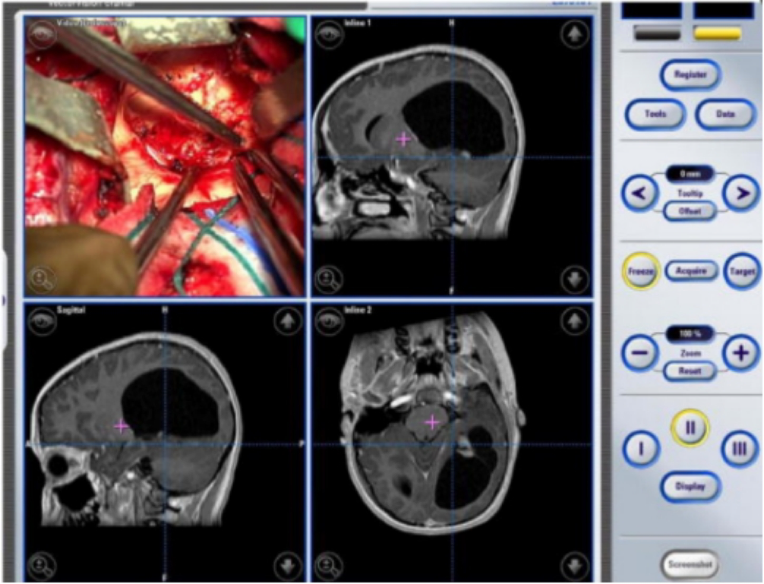

(艾文的左枕叶毛细胞性星形细胞瘤术中影像分析)

经过James T.Rutka教授手术团队的讨论,他们决定对艾文使用无框架立体定向术和术中神经导航手术,以确保他的病变完全切除。较终,手术结果得偿所愿,全切除也意味着良好的预后。